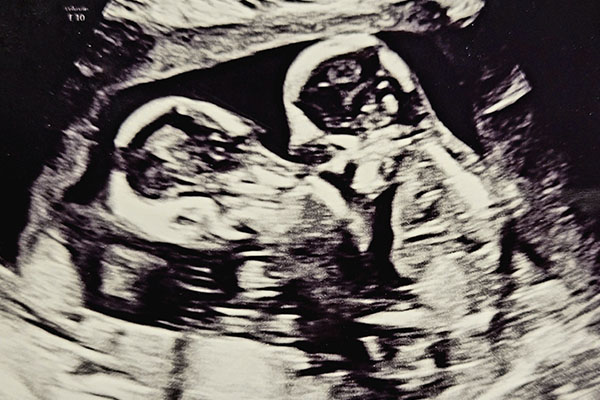

Een tweelingzwangerschap kan meer complicaties geven en daarom werden we meteen doorgestuurd naar het ziekenhuis. Bij de 8 wekenecho hoorden we dat het ging om een erg zeldzame en gecompliceerde mono-mono tweeling zwangerschap. Dat betekent dat de baby’s samen in één vruchtzak liggen, zonder vliesje ertussen. De baby’s delen de vruchtzak en de placenta. Dit brengt veel risico’s met zich mee, onder anderen dat de navelstrengen in elkaar kunnen raken. Daarom kwamen we onder begeleiding te staan van een academisch ziekenhuis.